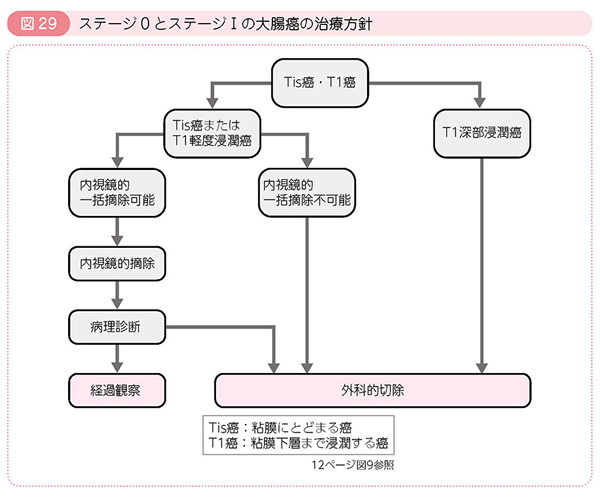

大腸癌frontier 6ー1 特集 腹膜転移 骨転移 脳転移の集学的治療

大腸がんの予後と5年生存率 医学的な病状の見通し がんのきほん